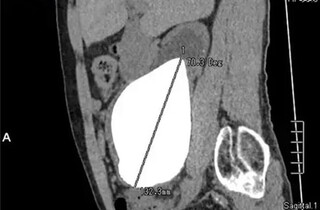

Вага конкременту склала 800 грамів, довжина – 13,37 сантиметра, а ширина – 10,55 сантиметра

Колишній військовослужбовець, 62-річний Каністуса Кунхе, переніс операцію в армійському госпіталі в місті Коломбо 1 червня. Хірург Кугадас Сутаршан, який проводив операцію, зазначив, що камінь був більший за нирку пацієнта – вага конкременту склала 800 грамів, довжина – 13,37 сантиметра, а ширина – 10,55 сантиметра. Попри значні розміри, за словами лікаря, камінь не заважав роботі внутрішніх органів.

Насамперед найбільшим в історії вважався конкремент, виявлений у нирці жителя Пакистану у 2008 році. Вага каменю складала 616 грамів.